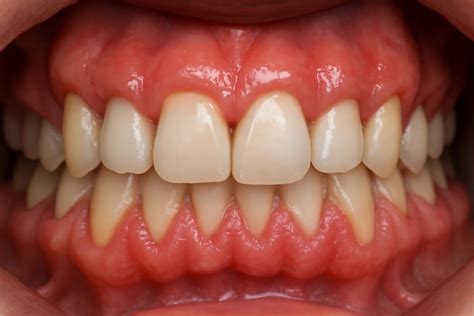

Extrusión dentoalveolar anterior

La sobreerupción de los incisivos superiores con su complejo dentogingival conduce a una posición más coronal de los márgenes gingivales y a una exposición gingival excesiva. Estos casos pueden asociarse a desgaste dentario en la región anterior (sobreerupción de incisivos compensatoria) o a mordida profunda. En los casos en los que existe mordida profunda, suele haber una discrepancia en el plano oclusal entre los segmentos anterior y posterior.

Exposición gingival excesiva debida a sobreerupción de los incisivos superiores. Puede observarse la discrepancia en el plano oclusal entre los segmentos anterior y posterior.

El tratamiento de estos casos incluye la intrusión ortodóncica de los dientes afectados moviendo hacia apical el margen gingival, corrección quirúrgica periodontal con o sin tratamiento restaurador complementario o un plan de tratamiento interdisciplinar completo.